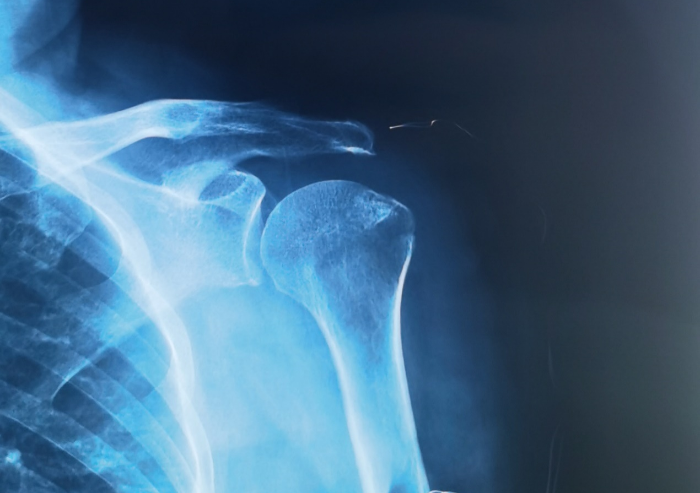

患者术前三维重建可见肱骨大结节撕脱骨折

患者术前CT表现可见大结节撕脱骨折